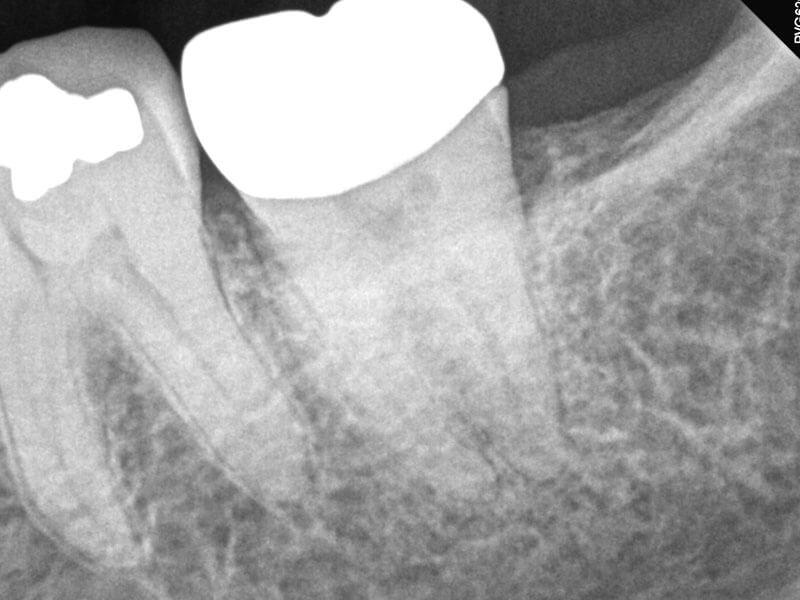

66-year-old female presented with history of spontaneous, intermittent pain in the lower left quadrant for three days, progressing to acute pain. No hot, cold or biting pain. Clinical testing revealed teeth in LLQ were negative to percussion, biting and grinding. Tooth #18 tested negative to cold, and other teeth in quadrant tested within normal limits to cold. Diagnosis: #18 necrosis and normal periapex. Treatment plan: RCT #18. Accessed, working length established, SlimShaper® ZS1 and ZS2 in distal canal and one mesial canal. Other mesial canal would not permit rotaries due to angle, so employed #15 hand file to length. GentleWave® Procedure with ProControl™ completed. Obturated with TruNatomy® 20 GP and BC Sealer HiFlow™. BC Liner™ over orifices.

Post